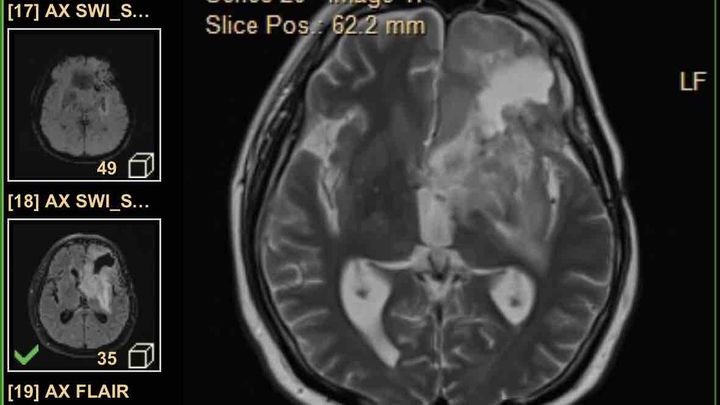

This is the family of Francisco Vega a great and hard working person who got diagnosed with Glioblastoma Cancer on January 2024. As the cancer progresses medical expenses has reached a very high amount and we are asking for financial support so we can continue paying for medications and chemotherapy plus transportation. His insurance unfortunately only covers a certain amount of everything. Just so you know a little about this cancer its the worst cancer that can happen to anyone unfortunately the survival rate is very very low with a 12 to 18 month after diagnosis. Everything and anything would be truly appreciated. Thank you